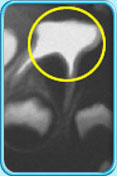

图中所见是一张X光片,显示一颗牙髓已坏死的乳臼齿。治疗前

图中所见是一张X光片,显示一颗接受了清除全部牙髓的治疗之后的乳臼齿。治疗后